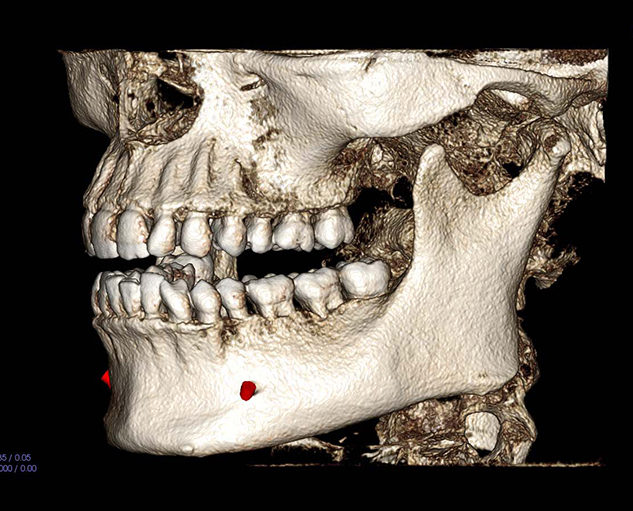

Teleradiology is an internet based radiology system wherein captured images from sources like X-Ray, CT Scan, CBCT Scan, MRI etc are sent to another location via web,so that an expert radiologist at another location can read the images for the purpose of generating reports and image portfolios.

About Us

Welcome to Rad Readers

Administered by the team of experienced radiologists who are established in the field of Maxillofacial Radiology and managing multiple radiology centres in different states of India.

Having faced the challenges of Maxillofacial Radiology in small and large cities alike, we completely understand the needs and expectations of clinicians and diagnostic centres..

Why RadReaders?

On every case submitted, we ask you to identify the clinical purpose(s). Radreaders has developed specific diagnostic objectives for each clinical purpose that will be addressed by the radiologist. This ensures that the report is relevant to your diagnosis and treatment planning.